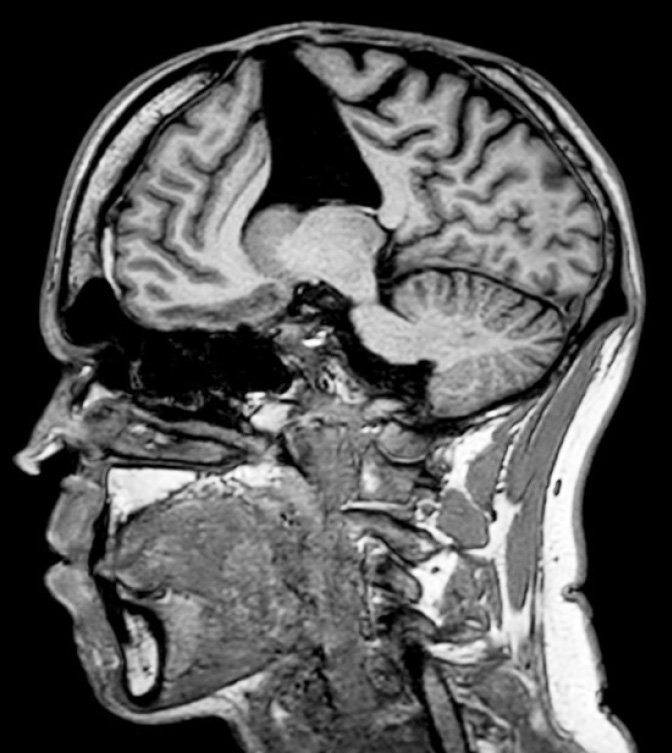

Testing of his cerebrospinal fluid results, as well as magnetic resonance imaging of his brain, found his condition was likely to be the result of iCAA.

Brain MRI scans showed multiple white matter changes, often associated with age, chronic hypertension, or small vessel disease.

They also showed numerous bilateral micro-haemorrhages.

Given the appearance of cortical micro-bleeds, and the history of exposure to cadaveric dural tissue, the researchers tested for iCAA.